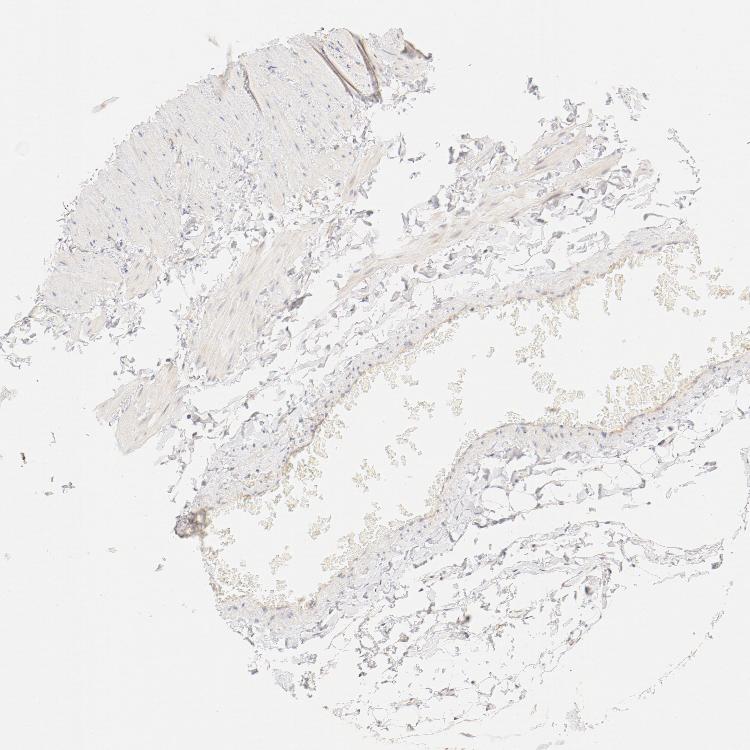

SOFT TISSUE 2 - Antibody stainingi

Antibody staining in the annotated cell types in the current human tissue is reported as not detected, low, medium, or high, based on conventional immunohistochemistry profiling in selected tissues. This score is based on the combination of the staining intensity and fraction of stained cells.

Each image is clickable and will lead to virtual microscopy that enables deeper exploration of all samples and also displays staining intensity scores, fraction scores and subcellular localization as well as patient and tissue information for each sample.

Antibody HPA003742Antibody CAB010443

Fibroblasts Not detectedLow

Peripheral nerve LowLow